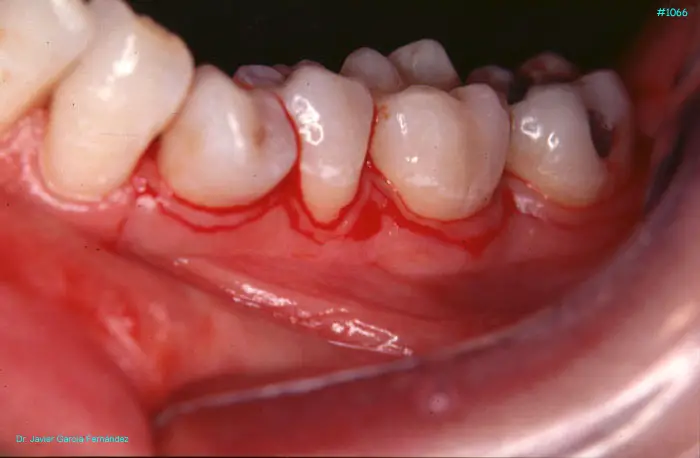

Atlas of Surgical Techniques in Periodontics. Chapter III. Atlas de Técnicas Quirúrgicas en Periodoncia

image436